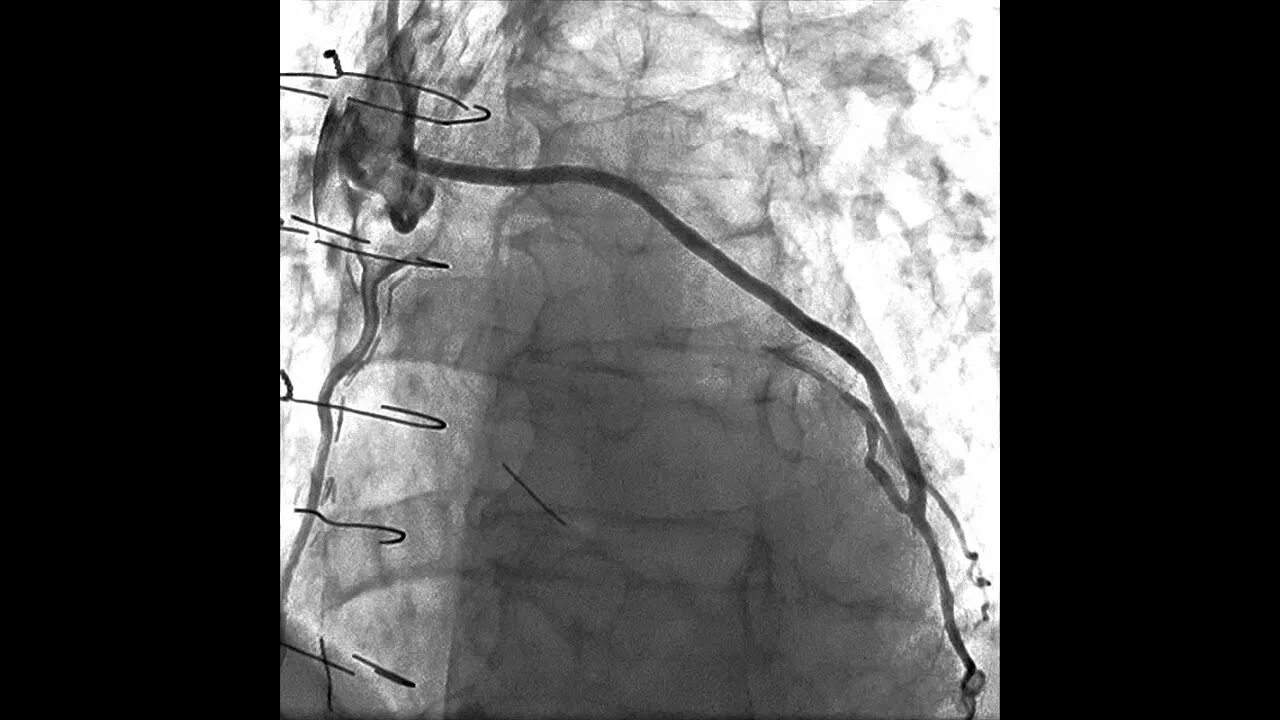

Стентирование самолет